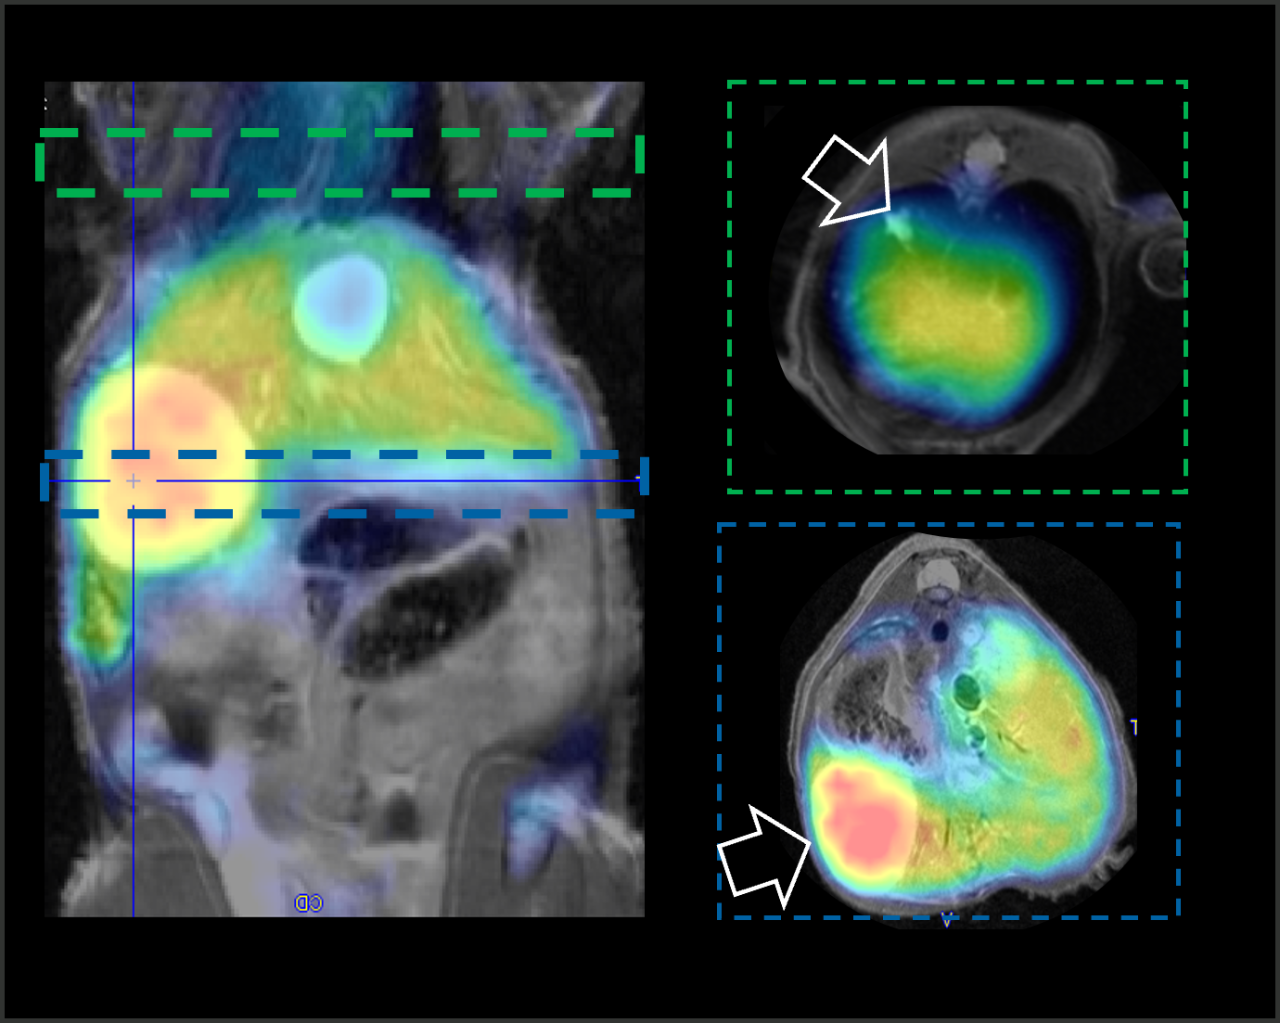

PET and MR in Mouse MetastaticTumor Model

(Left) Coronal whole-body PET/MR. (Right) Focused Axial PET/MR revealing location of lung and abdominal tumors.

Courtesy of Acknowledgements. Thanks to the Katherine Tucker, Mikayla Rodger, Dr. Lixin Ma, Dr. Carolyn Anderson, and Dr. Barry Edwards, MITC – Molecular & Imaging Theranostics Center, University of Missouri.